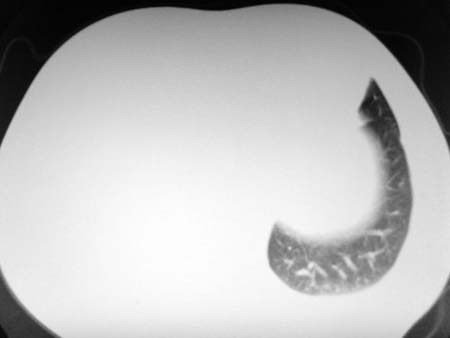

以下是引用qian在2008-4-27 17:02:00的发言:[br]考虑右下肺肺段隔离症伴有感染,建议做增强看看。

以下是引用zsl6918在2008-4-27 17:13:00的发言:[br]考虑右肺下叶炎性病变可能性大,建议抗炎治疗后复查,现有资料不能完全除外肺癌可能。